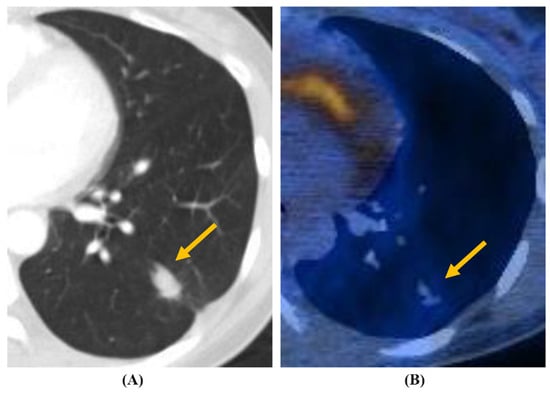

| PET uptake (SUVmax ≥ 2.5) (n = 20) | 18/20 (90) | 8 (40) | 10 (50) | 0.224 |